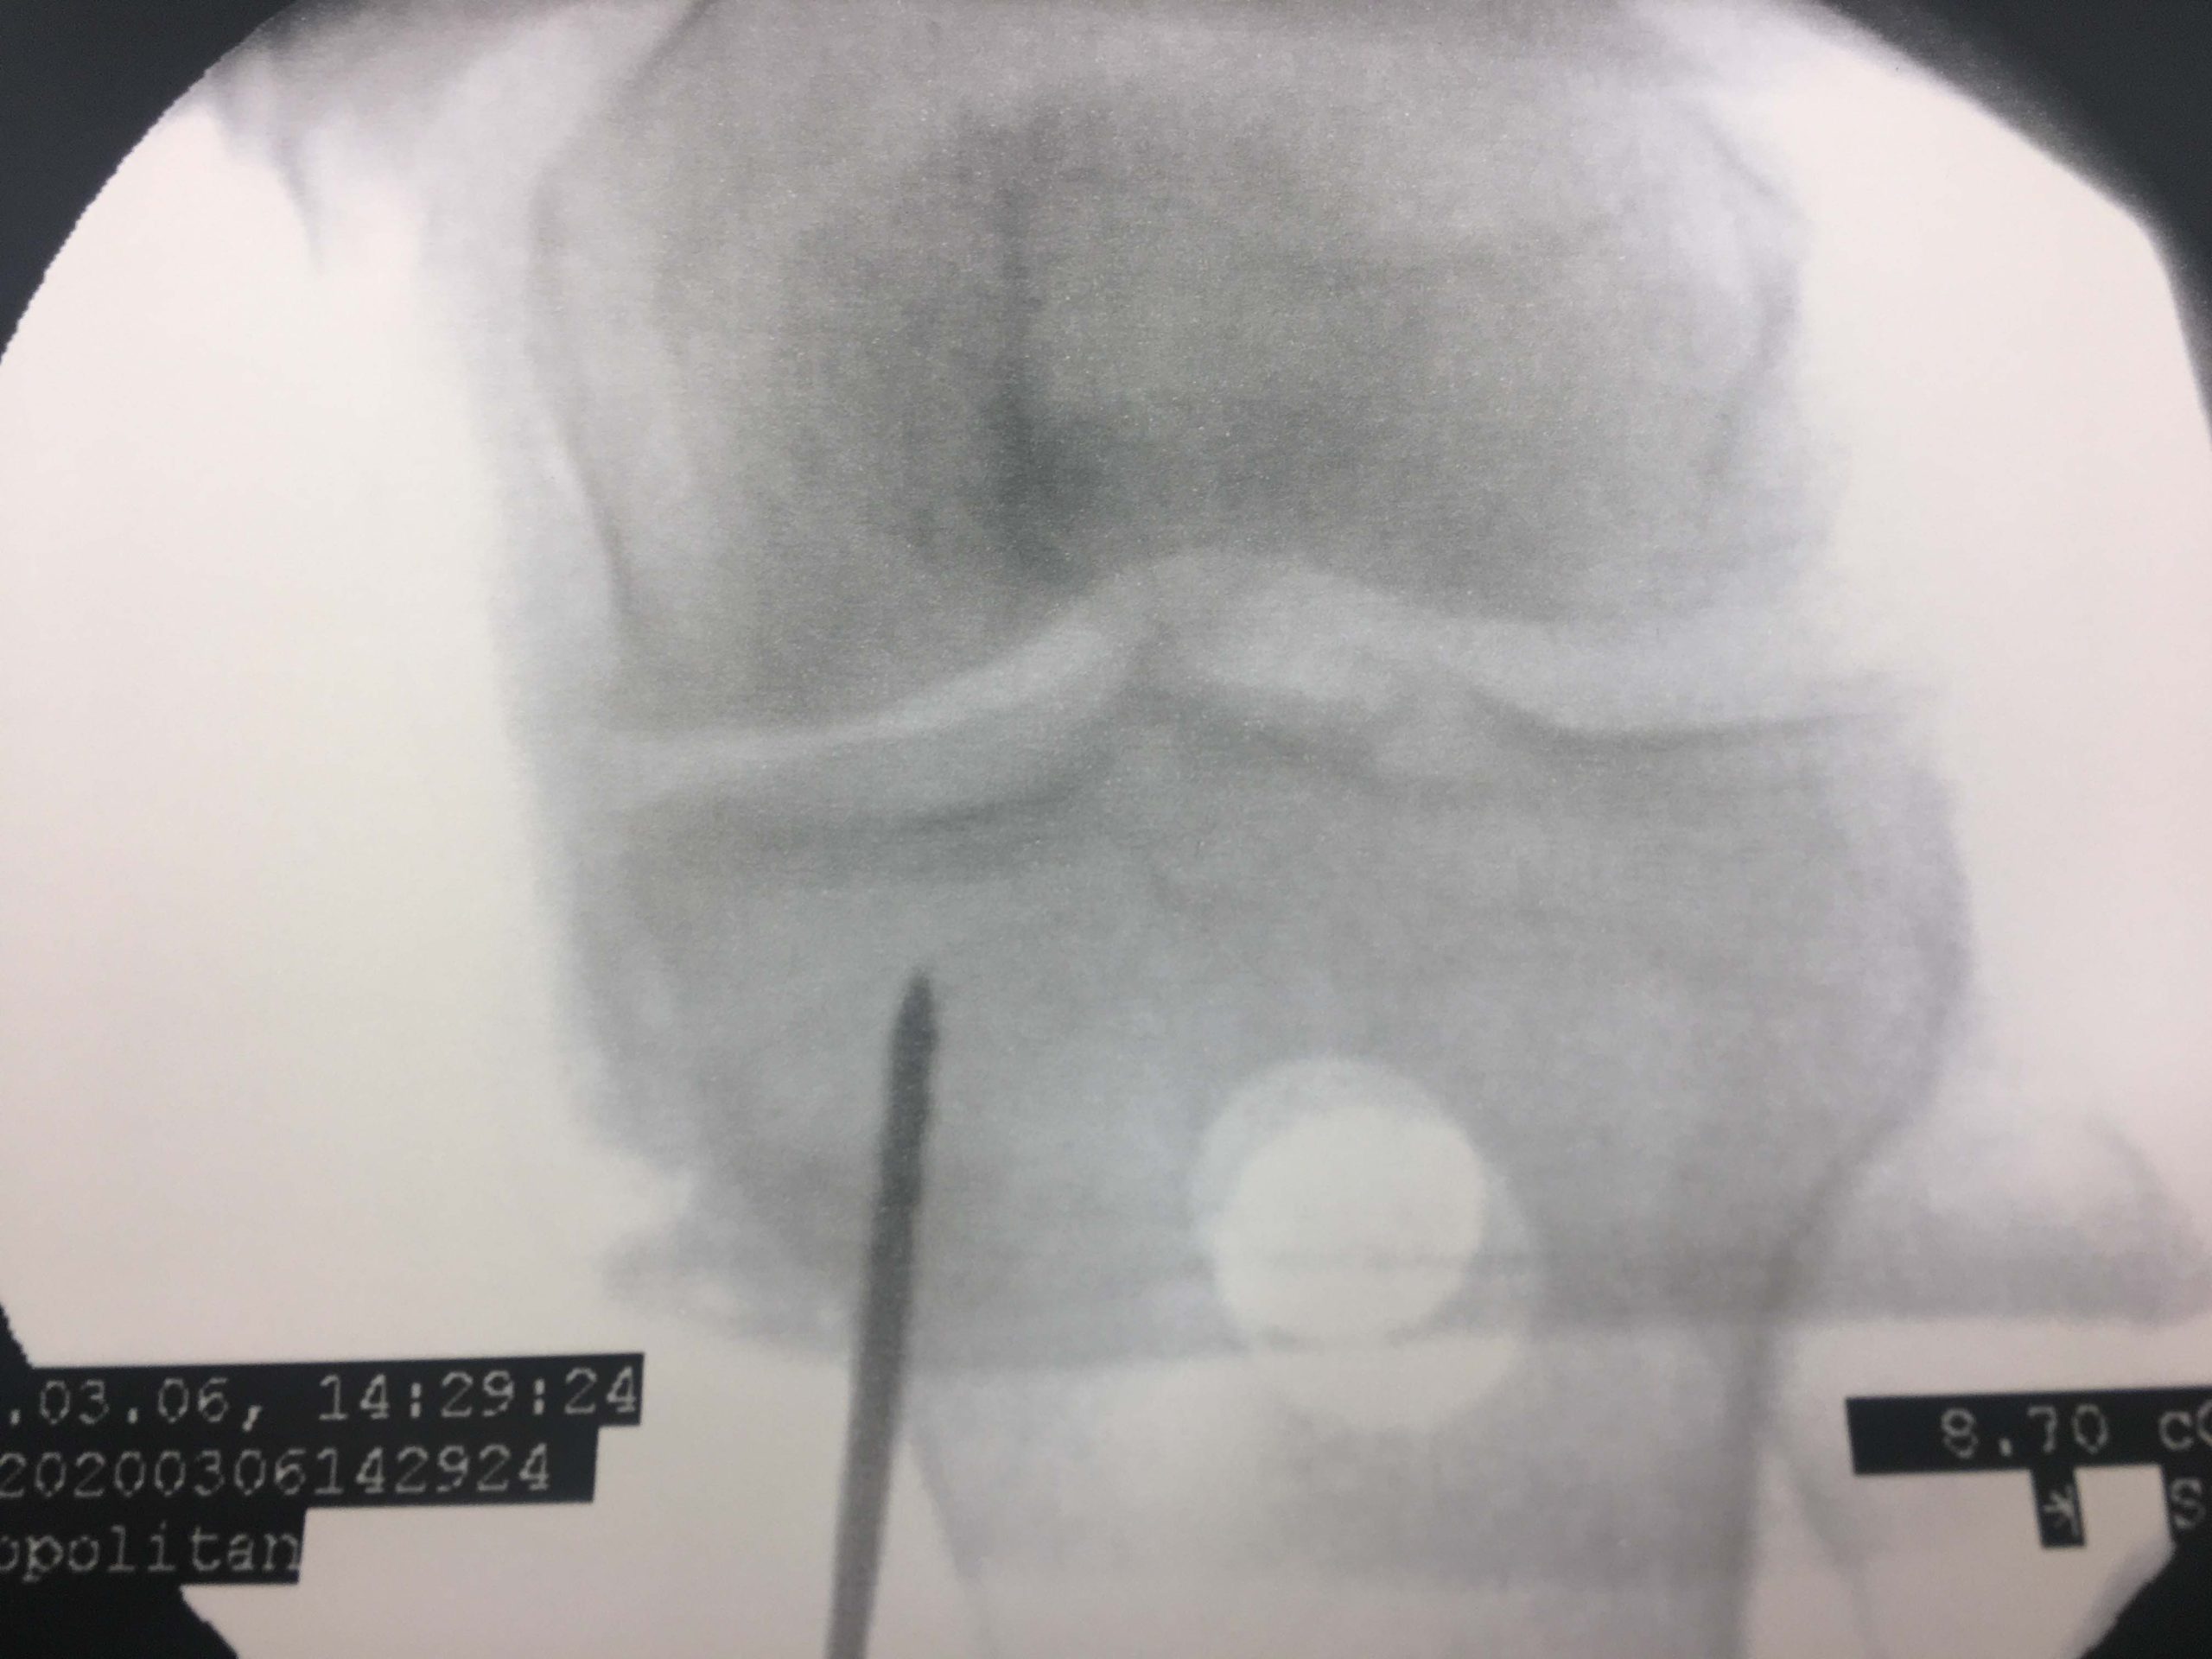

Εικόνα 3, α,β,γ, Περαιτέρω υπό ακτινοσκοπικό έλεγχο έγινε έγχυση 3ml Μεσεγχυματικών Βλαστοκυττάρων (MSCs) στον έσω μηριαίο κόνδυλο, 3ml MSCs στο έσω plateau της κνήμης καθώς και 5ml P.R.P. στην κατά γόνυ άρθρωση και διήθηση του έσω μηνίσκου.